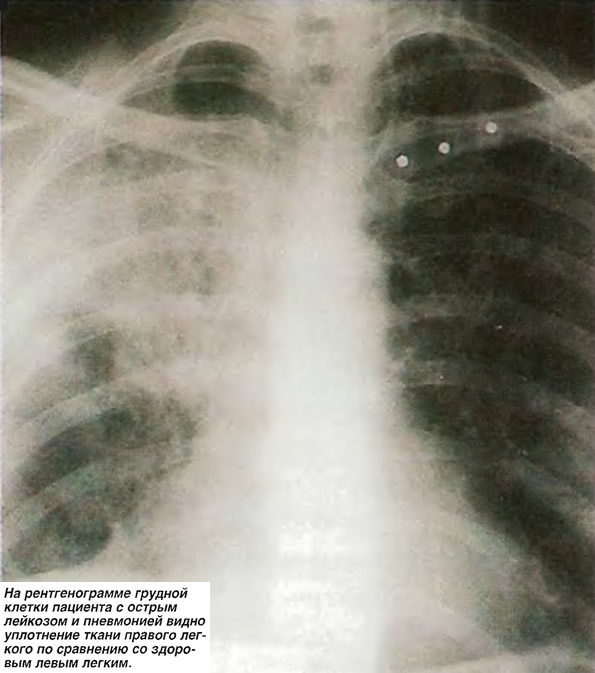

Снимок грудной клетки здорового ребенка: примеры и диагностика